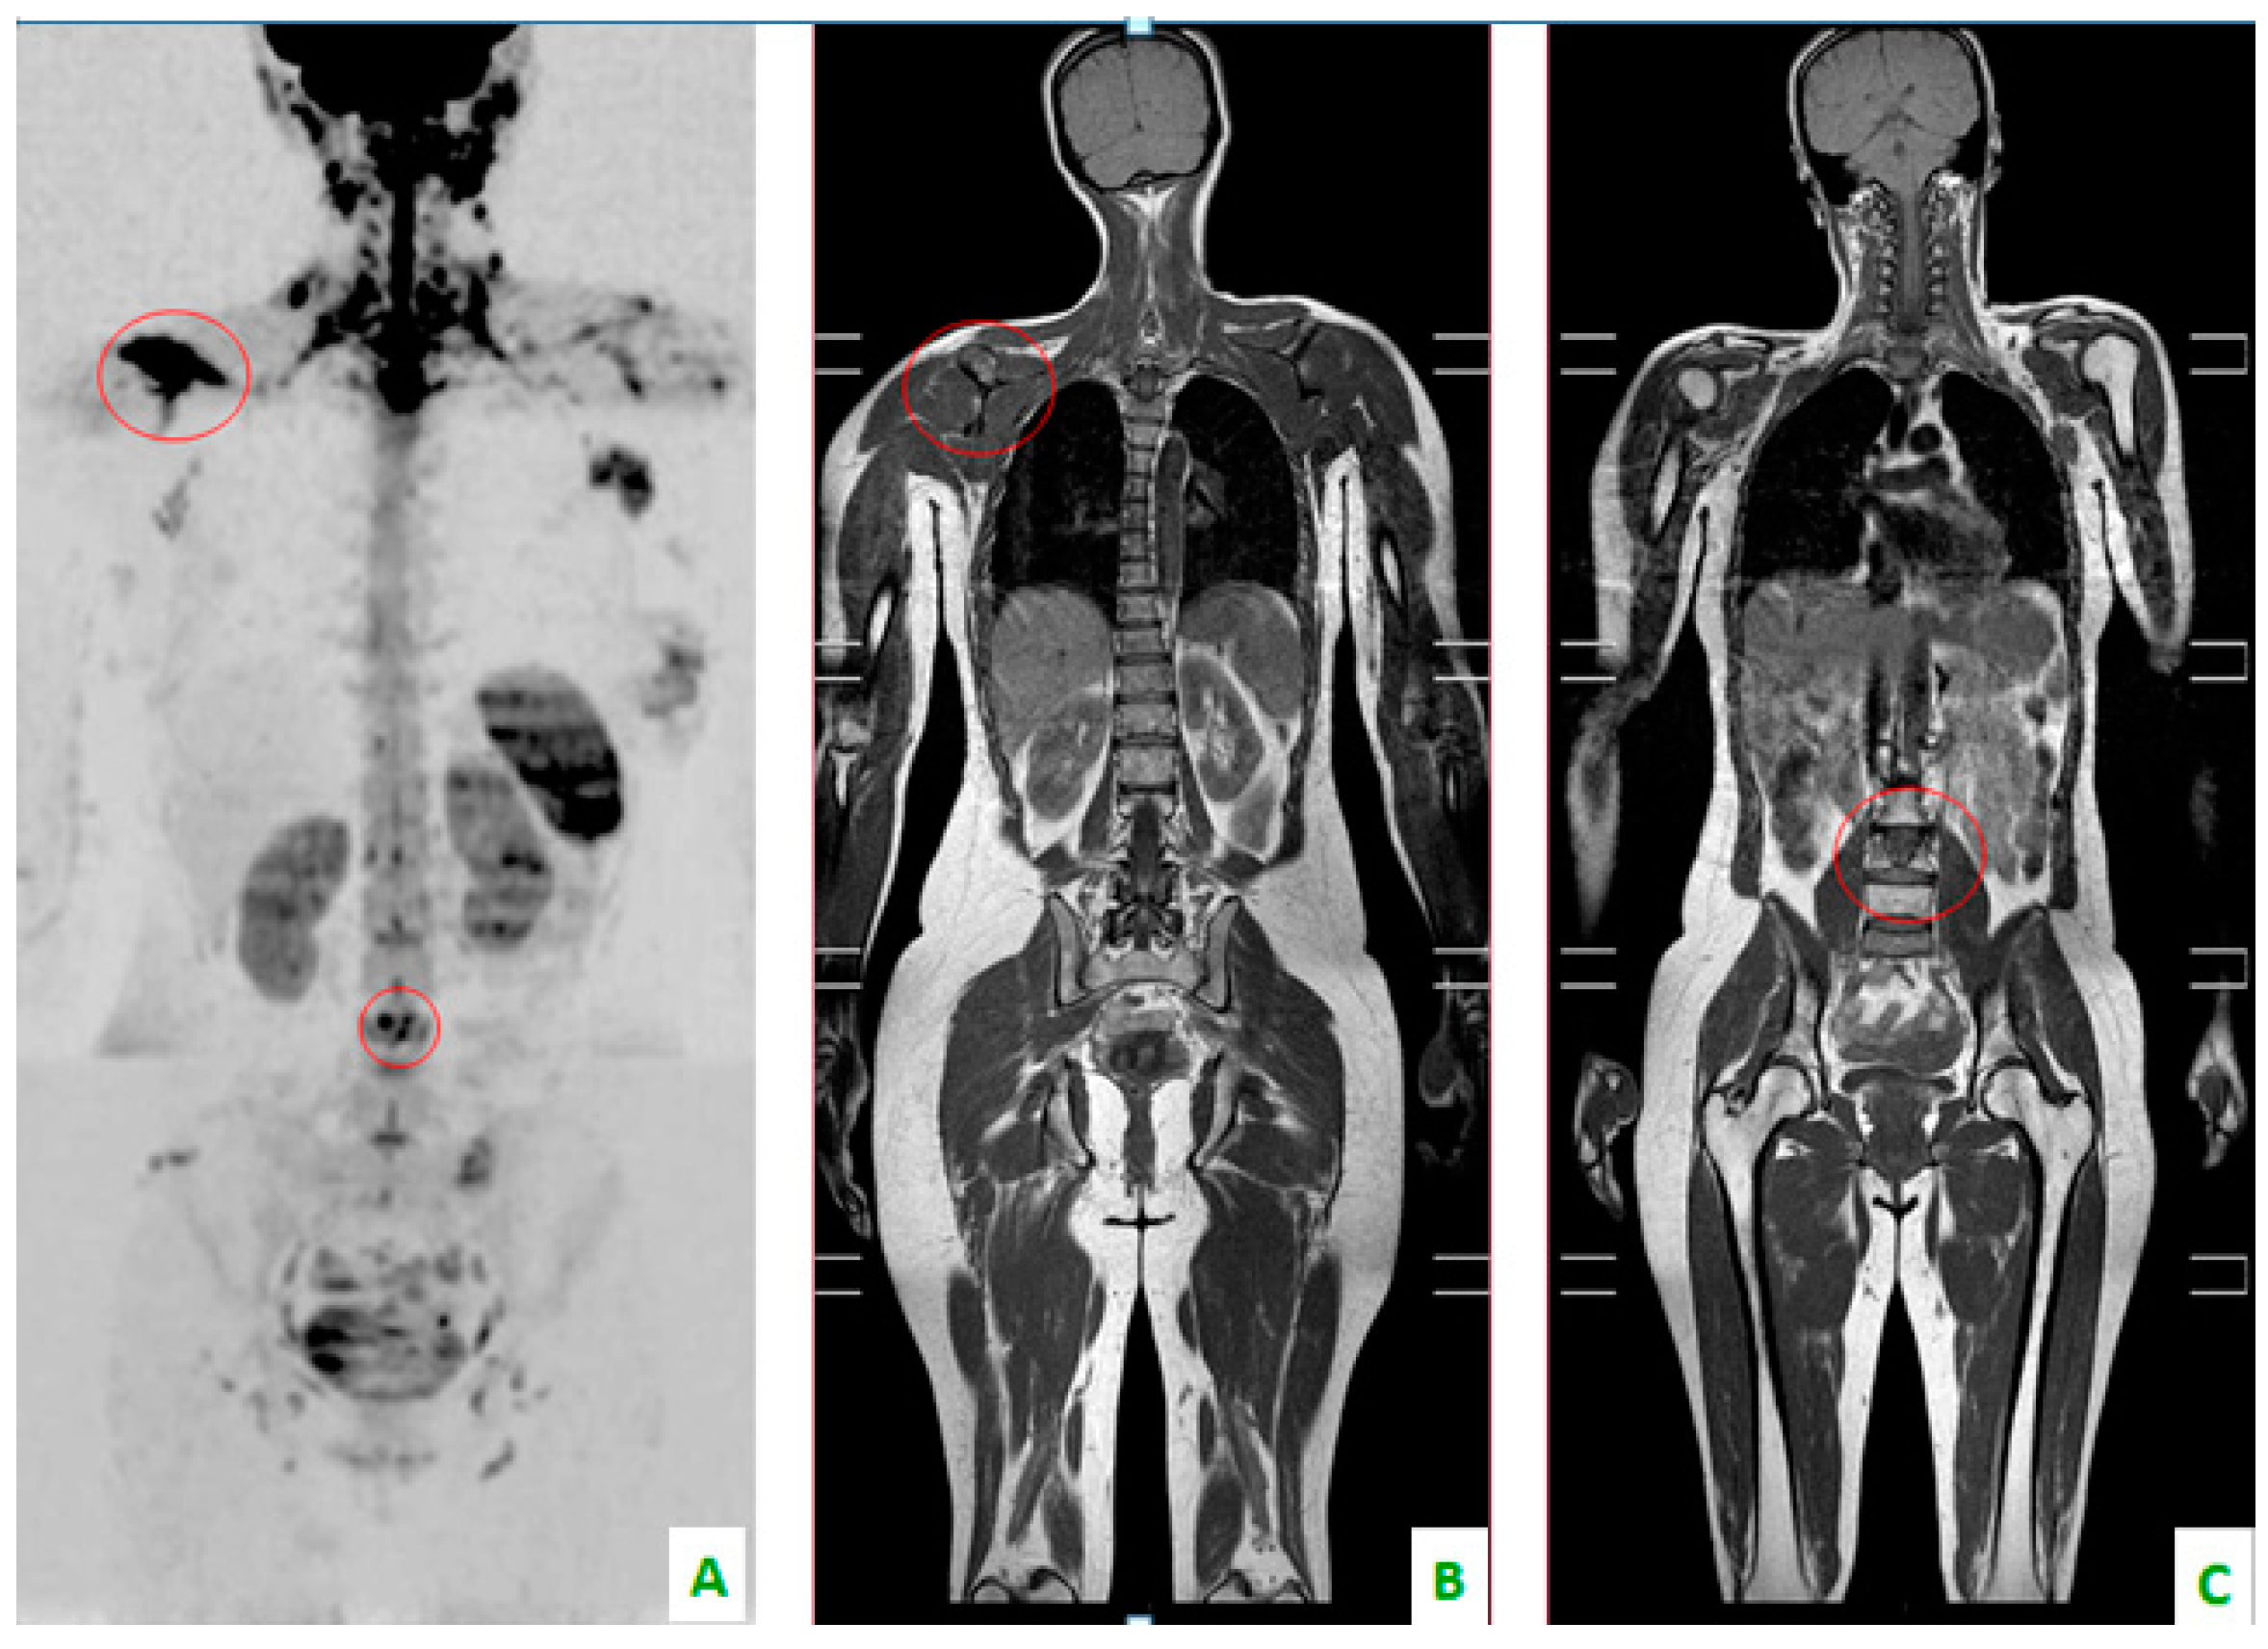

Figure 2. Bone localizations of breast cancer in the coronal plane: scapula and vertebral metastases (in the red circles). (A) DWI with a “positron emission tomography (PET)-like” view. The right scapula and one lumbar vertebra present an alteration of diffusivity. (B) T1 DIXON showing the hypointensity of the scapula and (C) lumbar soma.